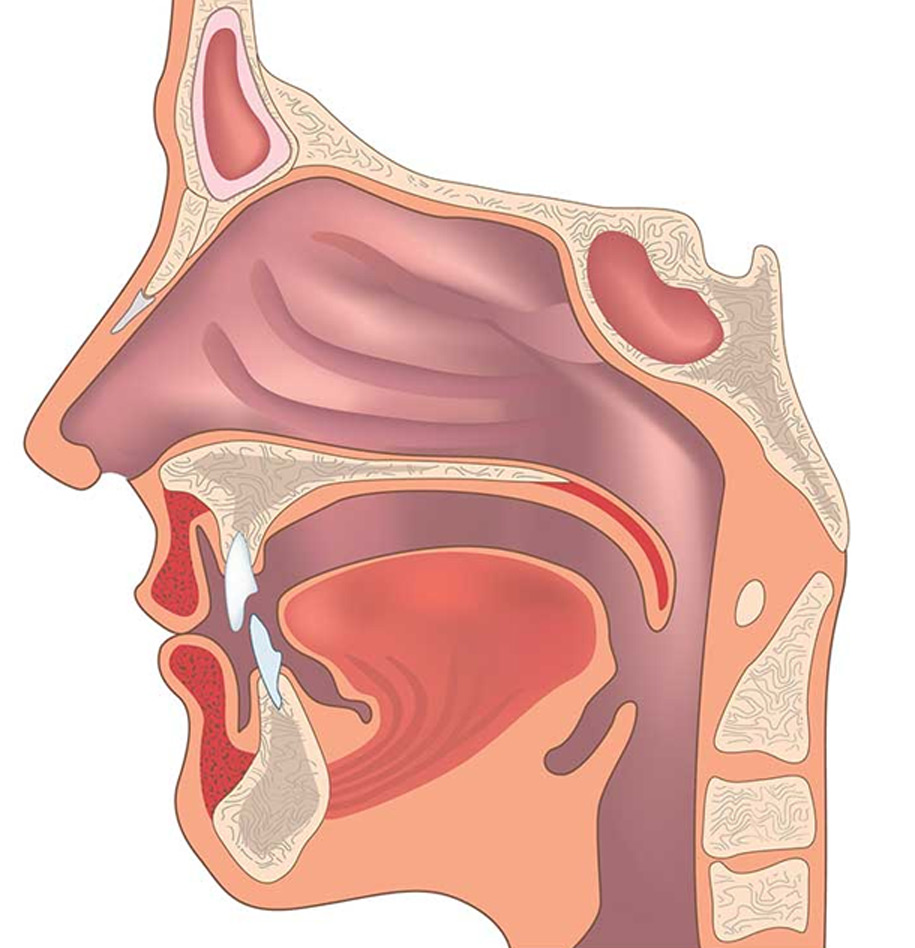

Normal appearance of pediatric subglottic airway. Note the convex Is Subglottic Stenosis A Respiratory Disease    subglottic stenosis (sgs) and tracheal stenosis (ts) are characterized by a narrowing of the airways.   learn about idiopathic subglottic stenosis, including symptoms, causes, and treatments. The goal of this study.   identify subglottic stenosis risk factors in patients, including a history of intubation, recurrent respiratory.  idiopathic subglottic stenosis (isgs) is a fibrotic disease of unclear etiology that. Is Subglottic Stenosis A Respiratory Disease.